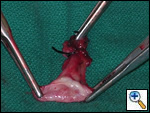

The patient was taken to the operating room where a standard median sternotomy was performed. Inspection revealed a left brachiocephalic vein that was completely obliterated and non-functioning. The SVC was normal at its junction with the right atrium, but at approximately mid level it was noted to be scarred and atretic to the level of the right internal jugular and right subclavian veins (Figures 2 and 3). Simultaneously the left saphenous vein, from inguinal canal to the ankle, was harvested endoscopically (Figure 4). Once harvested the vein was incised and opened longitudinally along its entire length. Using a standard 2-stage venous cannulae, a spiral vein graft was constructed using running 7-0 prolene suture, exchanging suture with each completed turn (Figures 5 and 6). The vein graft was left on the end of the cannulae and using a parachute technique an end-to-end anastomosis was first created in the distal SVC at the confluence of the right internal jugular and subclavian veins. The proximal anastomosis was constructed below the level of the obstruction at the entry area of the azygous vein. Following de-airing, inspection revealed the vein graft to be widely patent with no thrill or kinking (Figure 7). The patient was discharged home with coumadin with goal INR of 2.0 for 6 months. At six month follow-up, the patient reports significant improvement in her symptoms.

| Figure 2 | Figure 3 | Figure 4 |